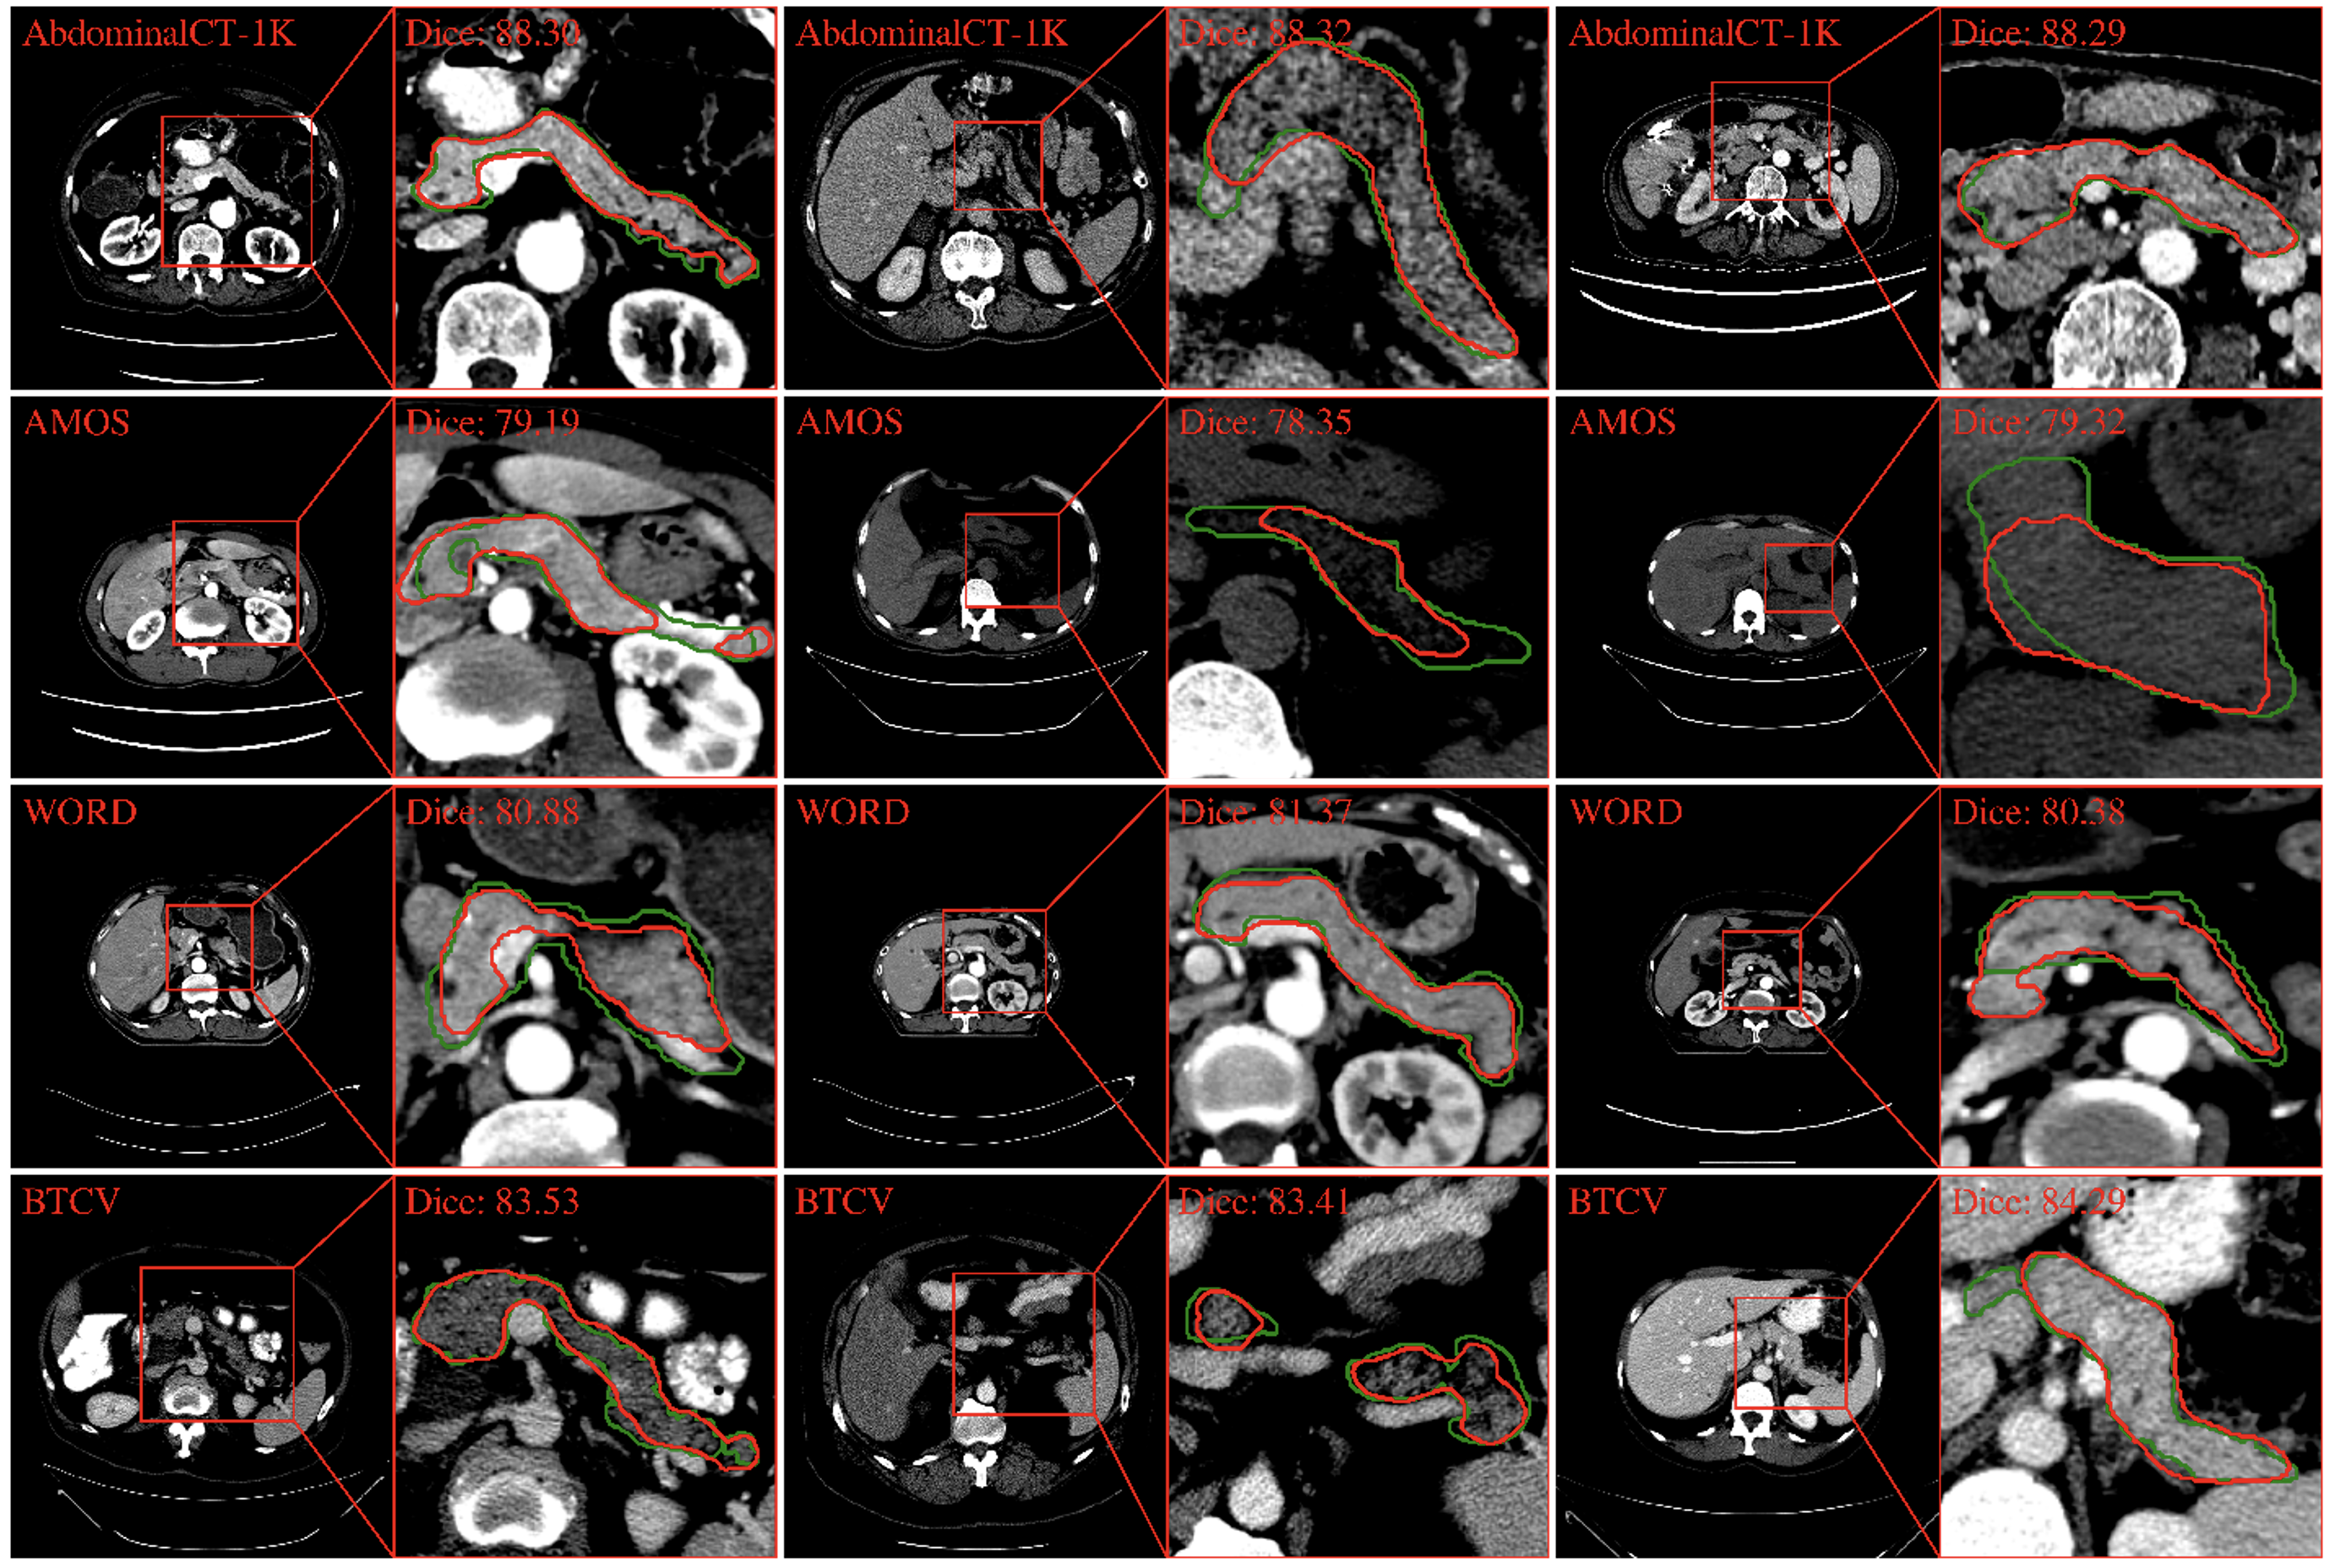

In the AbdomenCT-1K dataset, PanSegNet yielded an average Dice score of 88.31% with a standard deviation of 7.24% (median: 89.64%) and an HD95 distance of 5.10 mm with a standard deviation of 8.43 mm (median: 3.16 mm) (Table 4). Visual examination of the segmentation results, as depicted in Figure 4, demonstrates the model’s accuracy in delineating the intricate contours of the pancreas, closely aligning with the ground truth annotations. Segmentation performance dropped when our trained model was applied directly to AMOS, WORD, and BTCV external datasets. These datasets represent real-world clinical scenarios and potentially differ in distribution from the AbdomenCT-1K training data (domain shift). As expected, the model’s performance drops on these datasets, indicating the limitations of directly applying models trained on specific datasets to more diverse real-world settings. Specifically, the Dice coefficients decreased to 78.79% (-10.78%, p-value: 2×10-32), 80.89% (-8.40%, 6.13×10-25), and 83.71% (-5.21%, p-value: 6.05×10-4), respectively. These statistically significant decreases highlight the importance of addressing domain shift challenges when deploying models in real-world clinical applications. It is worth to note that despite the domain-shift challenges, PanSegNet obtains highly promising dice scores.

Refer to caption

Fig. 4: Segmentation results for CT pancreas across multiple datasets (green indicates the predicted pancreas, and red indicates the annotations). While AbdominalCT-1K exhibits robust segmentation performance, marked by precise boundary delineation, a domain shift is observed when extending the model to the AMOS, WORD, and BTCV datasets, underscoring the significance of addressing domain shifts for clinical applications. For a fair comparison, we select the visualization samples near the median value according to the Dice coefficient distribution (note: Dice is calculated volumetrically).